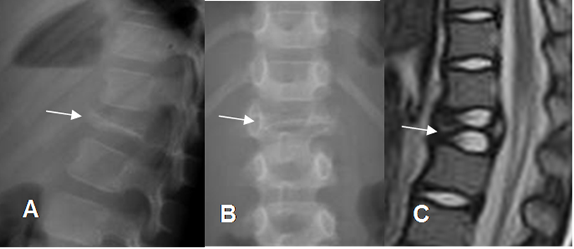

Fig 133. Granuloma eosinófilo.

A: Rx lateral, B: Rx AP, C: RM sagital en T2. Vértebra plana en L1, por granuloma eosinófilo.

En la columna la progresión de una lesión lítica, origina una vértebra plana, con preservación del disco y los elementos posteriores, con ausencia de masa de tejidos blandos. (13, 38). (Fig 133).